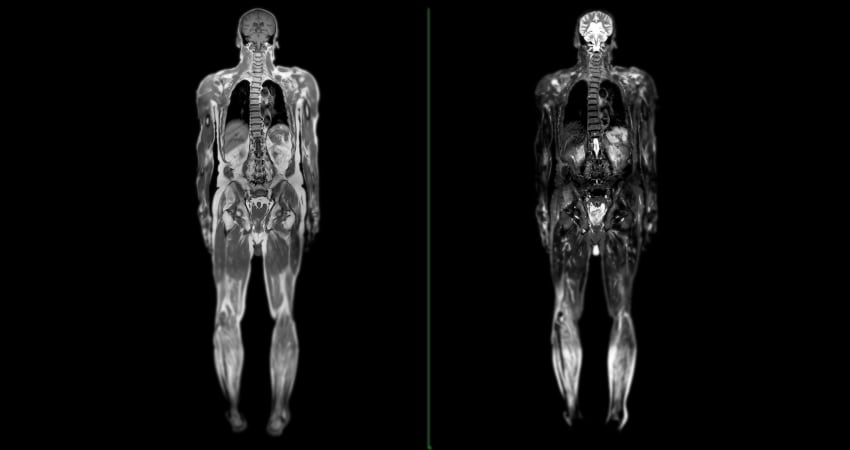

Celebrity-endorsed whole body MRI scans: medical advance or healthcare burden?

Whole-body MRI screening is booming in the private sector, yet radiologists and health economists say the scans will inevitably find abnormalities that lead to needless worry, wasteful investigations and diverted NHS resources.